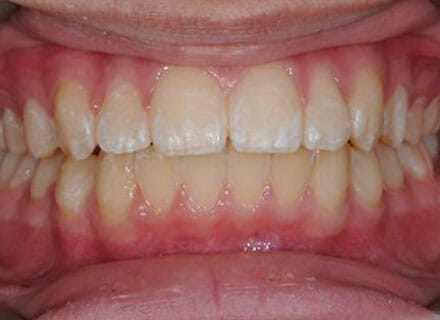

Fixing protruding teeth upper and lower and crowding – no extractions

this patient didn’t like the teeth because they pushed forwards and were sticking out and pushing out her lips. She thought that she looked like she had too many teeth and not enough space. In 12 months we pulled all the teeth back, pulled them together, and lined them all up. No teeth were extracted because we made room by expanding the jaws.